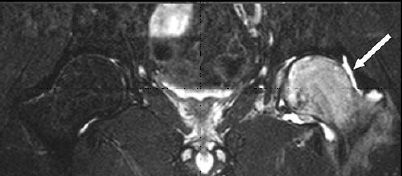

MRI scan showing edema

This MRI image shows edema surrounding the affected hip. Edema causes the bone to appear white in the MRI image.

Reproduced from Korompilias AV, Karantanas AH, Lykissas MG, Beris AE: Transient osteoporosis. J Am Acad Orthop Surg 2008; 16:480-489.

Bone Marrow Edema

One of the most common signs of transient osteoporosis of the hip is bone marrow edema. Bone marrow is a spongy substance that produces blood cells and is located in the hollow part of long bones. In bone marrow edema, the bone marrow is inflamed and full of fluid.

An MRI scan of a hip affected by transient osteoporosis will usually reveal bone marrow edema. Because of this, MRI is one of the most useful studies to help diagnose the condition.